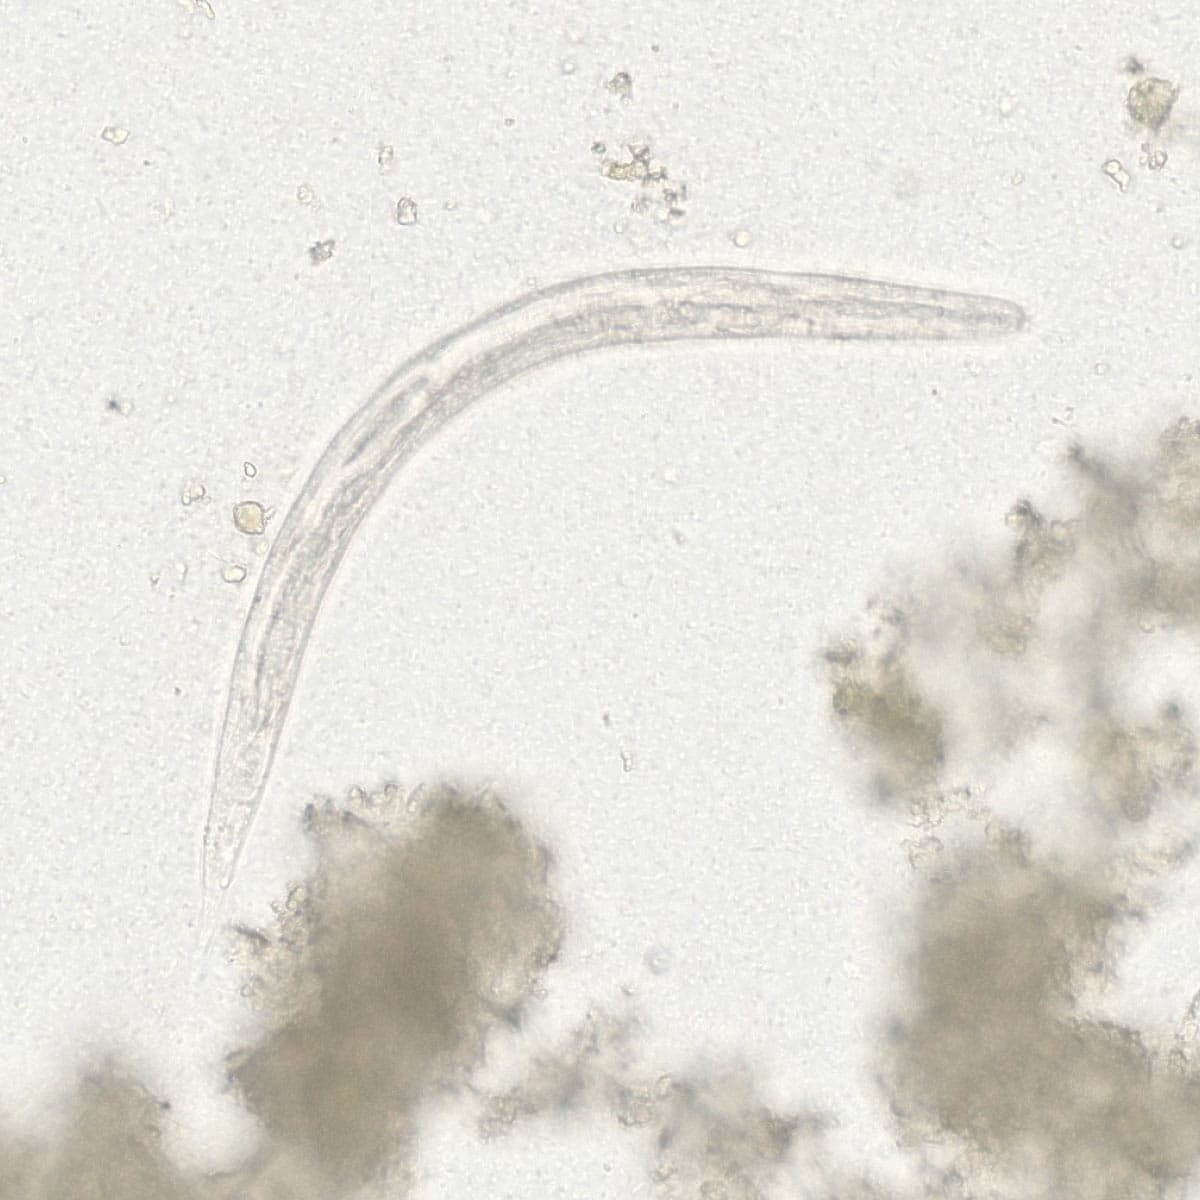

Automatic detection of rare species

Built on worldwide parasite-positive specimens, ParaScout AI identifies a vast number of parasite species, including those that are clinically rare or challenging to find.